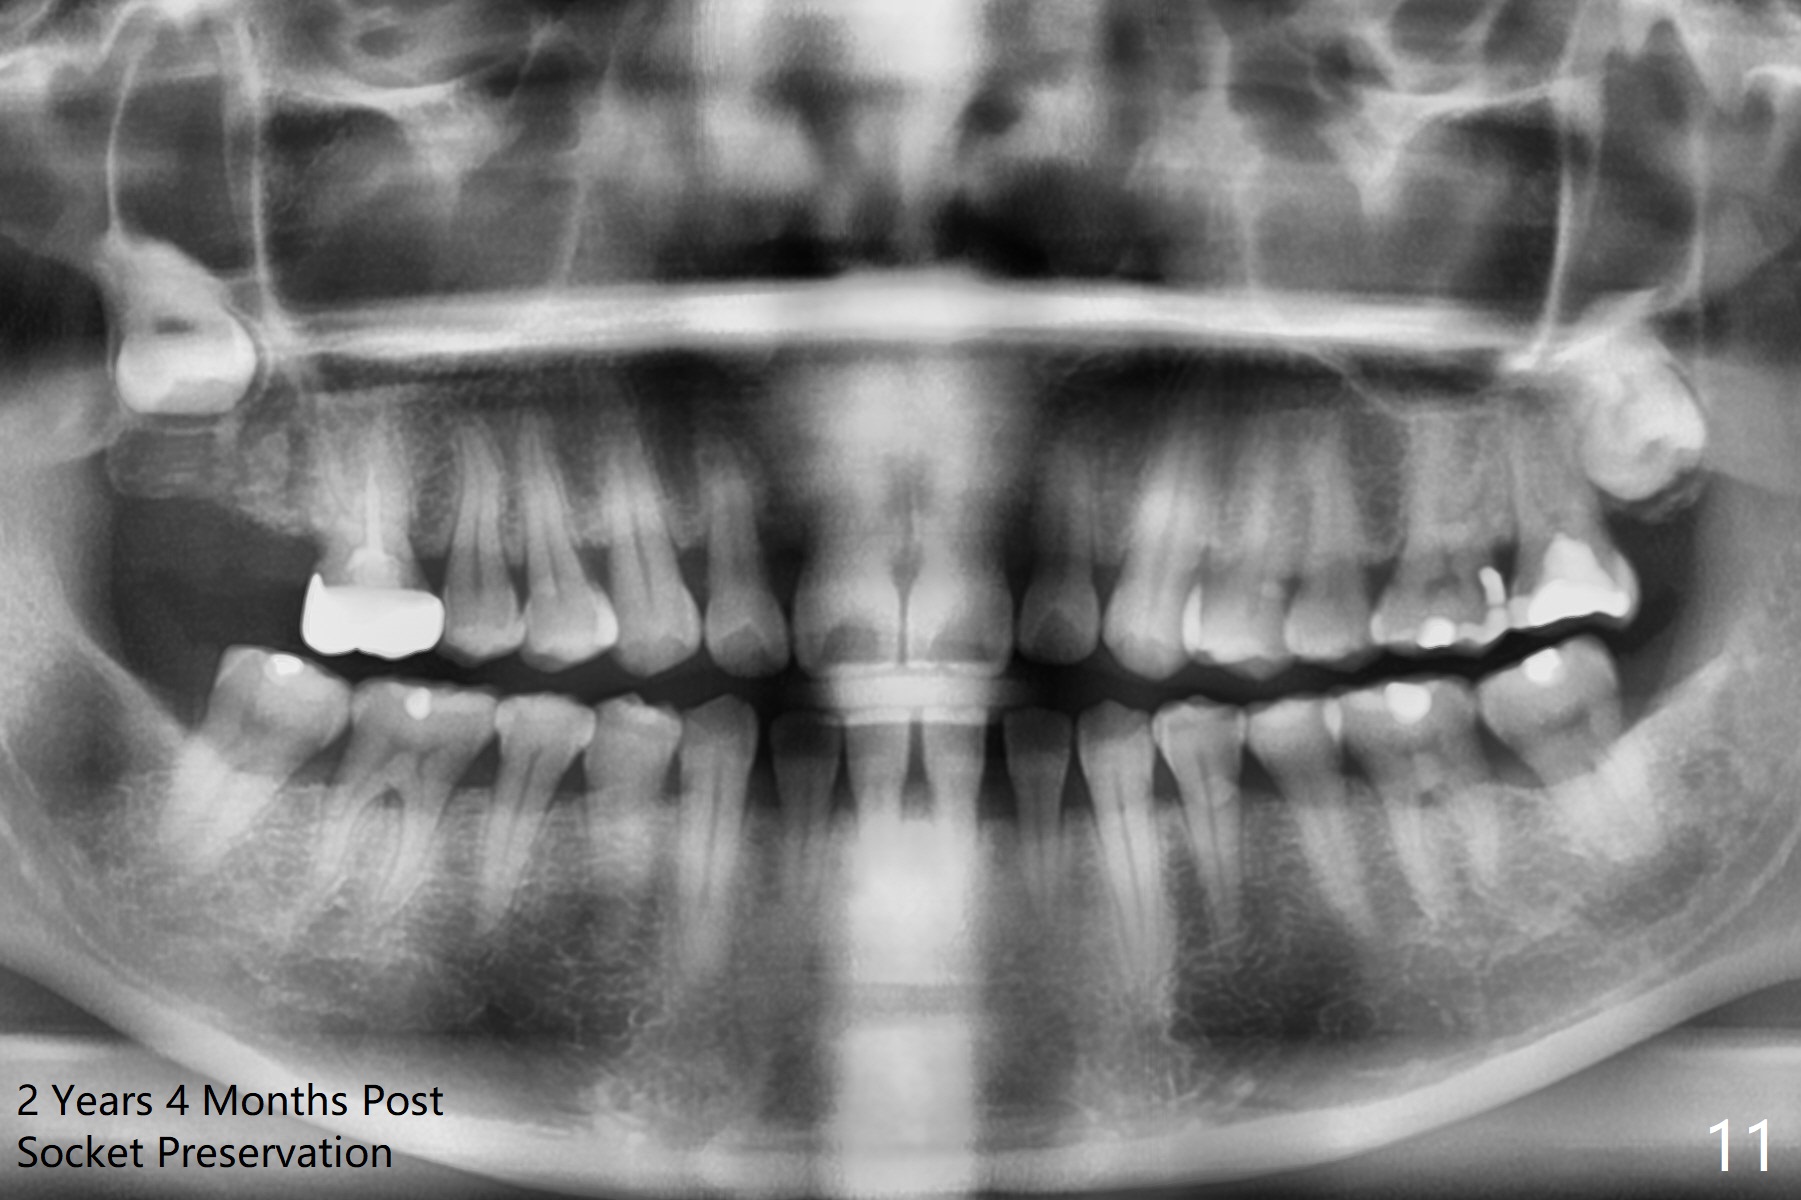

The socket of #2 heals 13 days postop; it appears that the bone graft remains in place (Fig.7,8 *). The patient is instructed to return in 3-4 months for impression and CT for guide. The socket heals 4 months postop (Fig.9,10). She plans to have implant next year, since she wants to add another insurance. The patient returns for implant without removal of the third molar 2 years 4 months post socket preservation (Fig.11). A 5x7.3 mm implant can be placed without invading the sac of the impacted third molar (Fig.12). In fact the lab has a better plan. A lump of bone forms in the previous socket 1 year 4 months postop (Fig.13 *). The ridge is wide and dense (Fig.14). A narrow implant placed oblique could be longer (Fig.15), as compared to a wide, short one (Fig.12).